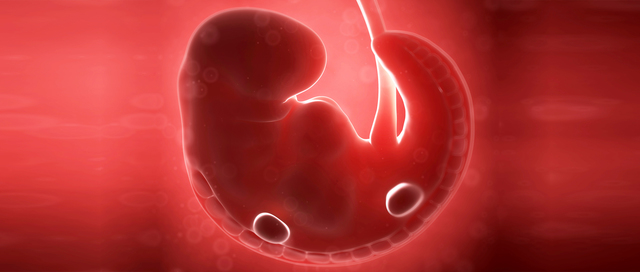

Surge cuando los espermatozoides(300 millones)penetran la tuba uterina y ahí sufren el proceso de capacitación , despúes se mueven por quimiotaxis hacia el ovocito secundario que se encuentra en las trompas de Falopio, donde pasa la fecundación, despues pasa la reacción acrosomica que le va a permitir la entrada a el ovocito, se produce la onda de calcio que hace que el ovocito siga su ciclo celular,la fecundación se concluye cuando hay una union del pronucleo femenino y masculino

• Period: to

1era SDG

El ovocito secundario se va a expulsar en el periodo de ovulación de la mujer , si no ocurre la fecundación este se degrada de 12-24 hrs por que no completa su segunda división mitotica, la cual tiene lugar cuando sucede la onda de calcio que hace que se forme un cuerpo polar también llamado pronucleo femenino, el cual cuando se une con el masculino sucede la fecundación , el cigoto va a secretar hCG el cual va a hacer que se mantenga el cuerpo luteo de la madre y no haya menstruación